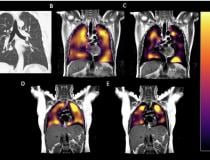

This photo gallery shows the variety of radiological presentations of COVID-19 (SARS-CoV-2) in medical imaging, including computed tomography (CT), radiograph X-rays, ultrasound, echocardiograms and magnetic resonance imaging (MRI). The radiology images show examples of typical COVID pneumonia in the lungs and the numerous complications the virus causes in the body in multiple organs, including the brain, kidneys, heart, abdomen and vascular system.